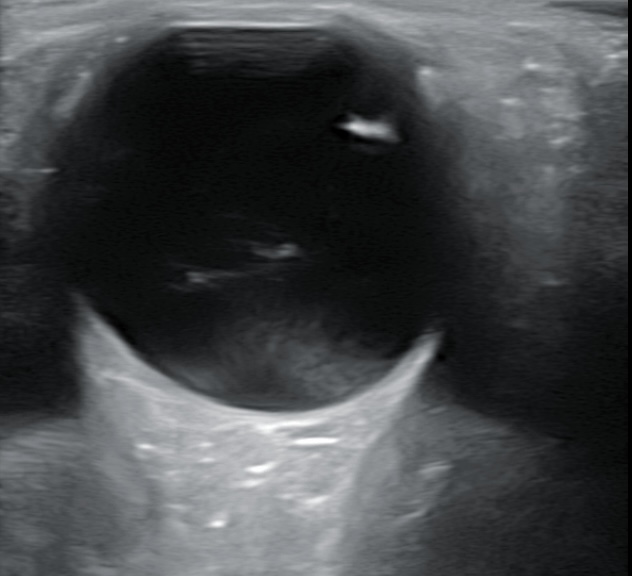

Hallazgos ecográficos

Se realiza ecografía donde se aprecia DVP en ojo derecho sin descartar hemovitreo y en campo superior y nasal una membrana más gruesa.